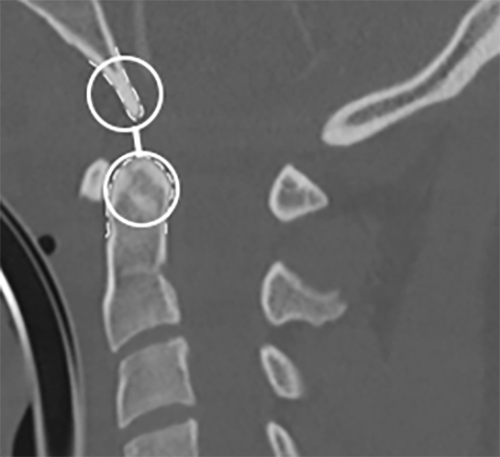

An os odontoideum (OO) is another mimicker of spinal trauma. An OO represents a congenital anomaly of the C2 vertebra. (See Figure 2.) The OO is an independent bony ossicle of variable size and shape that is a separate entity from the odontoid process.27 The OO can be either orthotopic (sitting in normal position above the odontoid process) or a dystopic os (fused to the basion).

Figure 2. Demonstration of an Os Odontoideum on Sagittal Cervical Spine Computed Tomography |

|

The arrow points to an identified os odontoideum. Courtesy of Joy Hallmark, MD. |

There is significant debate regarding the etiology of an OO. Whether this represents a congenital anomaly or the sequelae of a remote trauma has yet to be determined.28 An OO can be distinguished from an acute fracture based on imaging, including lateral cervical spine X-ray and CT, by having a smooth, regular border and in the typical location described. Since this may result from a nonunion of the secondary ossification center at the tip of the odontoid, the location can help distinguish an OO from acute fracture.29

Once the diagnosis of an OO is made, a thorough neurologic exam is vital. Despite possibly being congenital in nature, OO can become symptomatic even with minor or no history of trauma. Symptoms frequently present in late adolescence with neck pain, shoulder pain, and headaches. Even severe symptoms, such as myelopathy and those of vertebrobasilar ischemia, have been reported. This is hypothesized to be caused by slow progression of AA instability.27

In contrast, an acute odontoid fracture typically occurs in high-energy mechanisms in younger patients. These fractures occur because of cervical hyperflexion or hyperextension in the setting of blunt trauma.

In very young patients (younger than 10 years of age), the fracture typically occurs at the site of the basilar synchondrosis. Odontoid fractures are the most common fractures of the atlas and account for nearly 15% of all cervical fractures.29 Similar to evaluation of an OO, a detailed neurologic exam is vital when evaluating an odontoid fracture. (See Figure 3.)